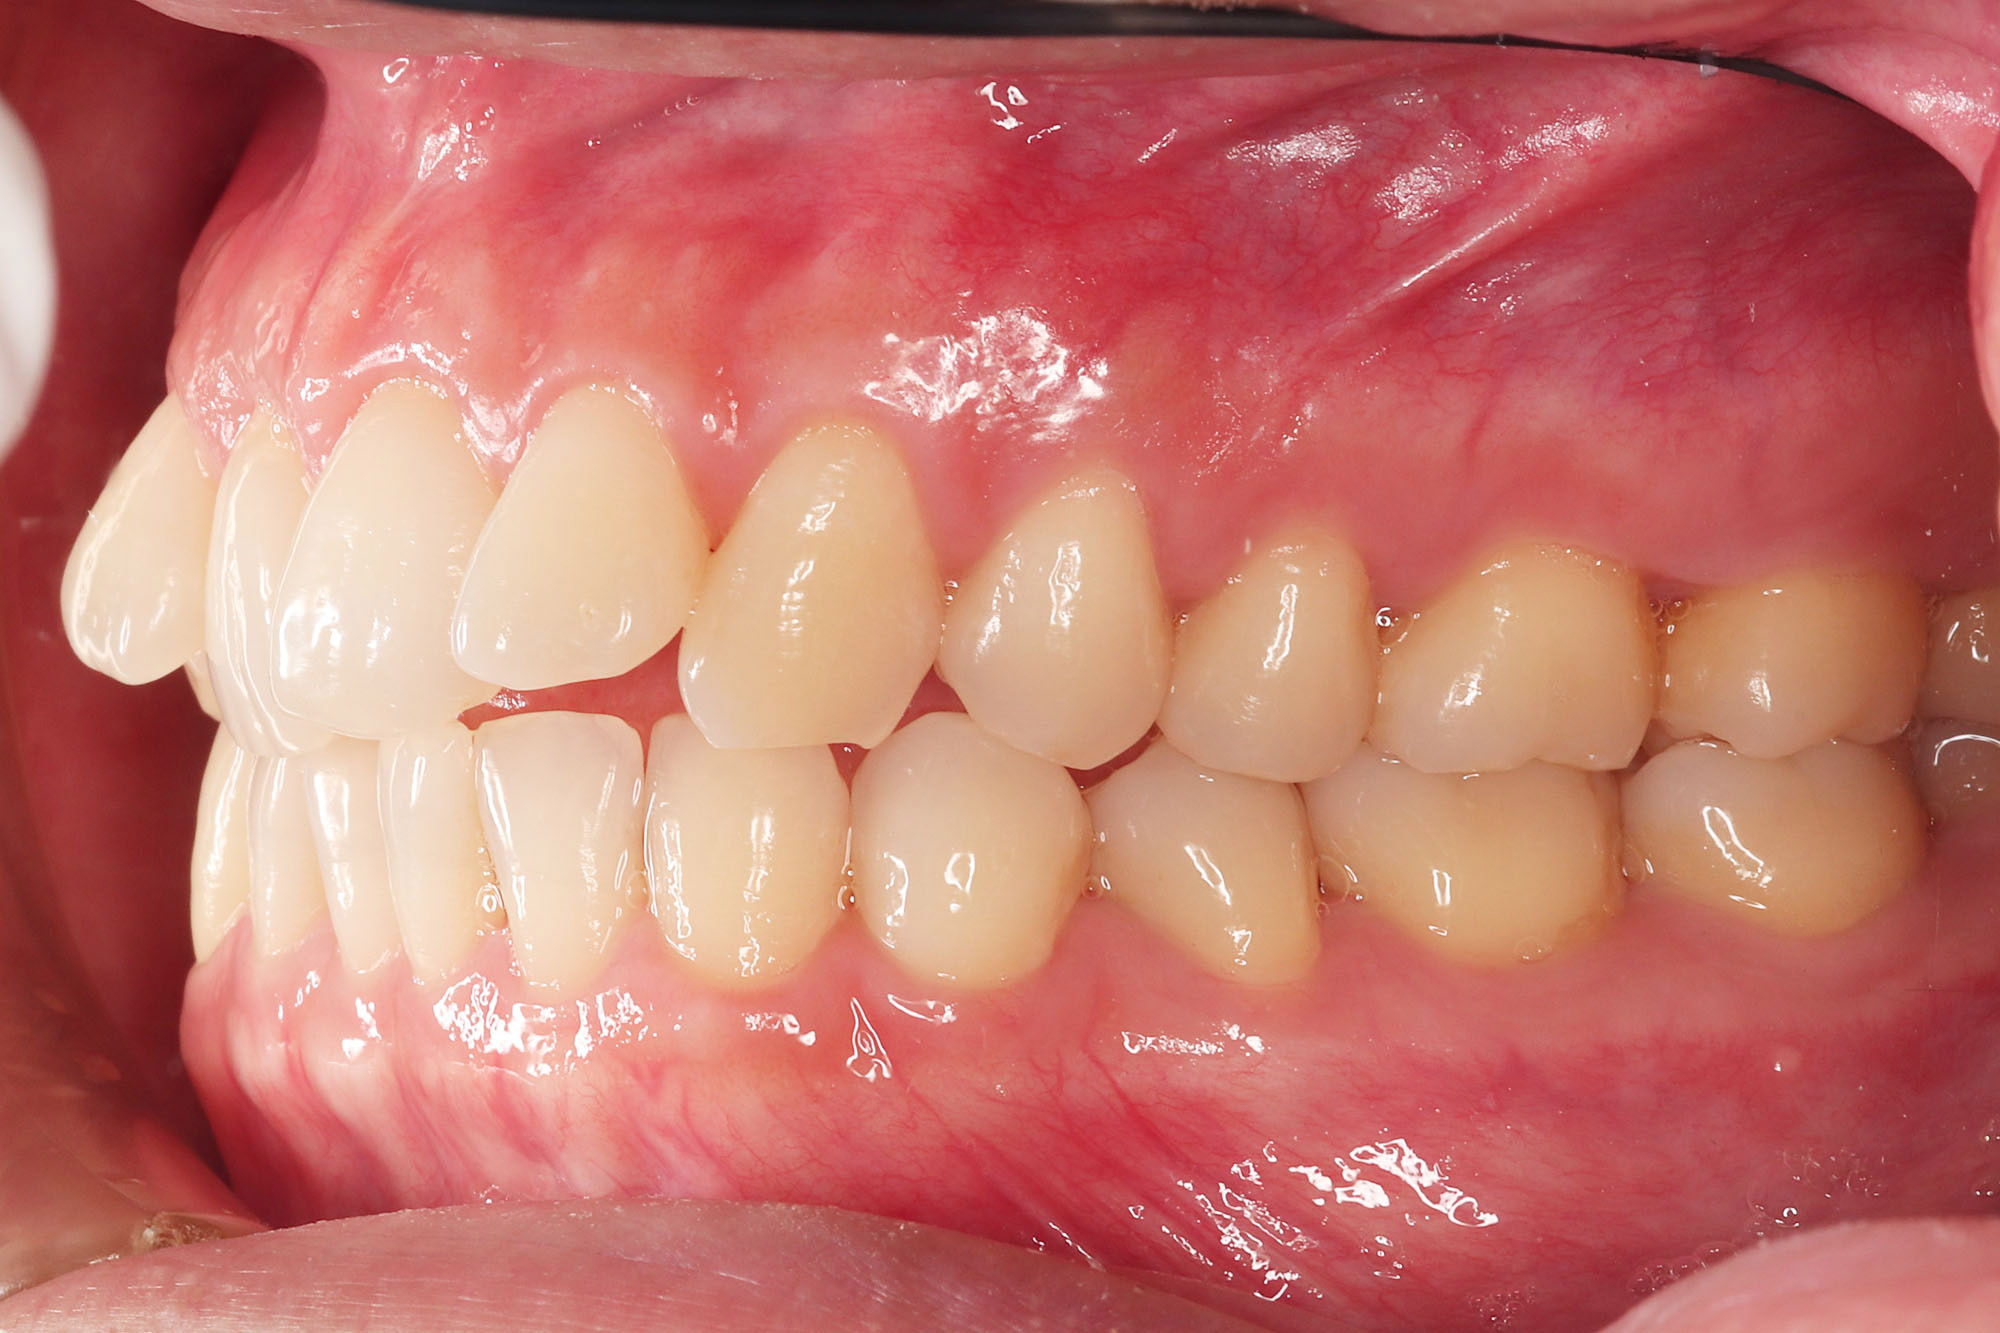

治療後

after

患者の症状 上顎前歯の前突、八重歯

治療方法 上下左右の第一小臼歯抜歯で、マウスピース型カスタムメイド矯正歯科装置による矯正

治療結果 上顎前歯の前突、八重歯が改善されました。

歯並びをより良くするために追加でアライナーを発注しました。

リスク/副作用 決められた時間装着する必要があります。